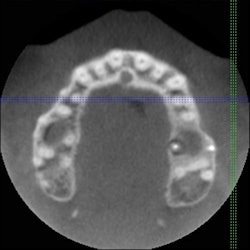

![]() |

| Cone beam CT images can provide axial views not possible with traditional 2D imaging. |

Also with a single-arch scan, sinus infections or abnormal sinuses can be shown to the patient. For example, a patient who has had an infection in the upper first molar had complications with the sinus that was easily detected with a 4 cm single-arch scan. By viewing the opposite side, the sinuses were clear in one side while the arch in question had some type of irritation present in it. Also with a full-arch scan, another patient had a break in the sinus and the infection was draining right into it.